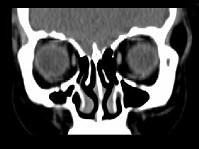

问题 女,31岁,在左眶外上缘发现一包块,质软,余所见无明显异常.如图所示病灶应诊断为()

选项 A.畸胎瘤 B.错构瘤 C.脂肪瘤 D.表皮样囊肿 E.淋巴管瘤

答案 C